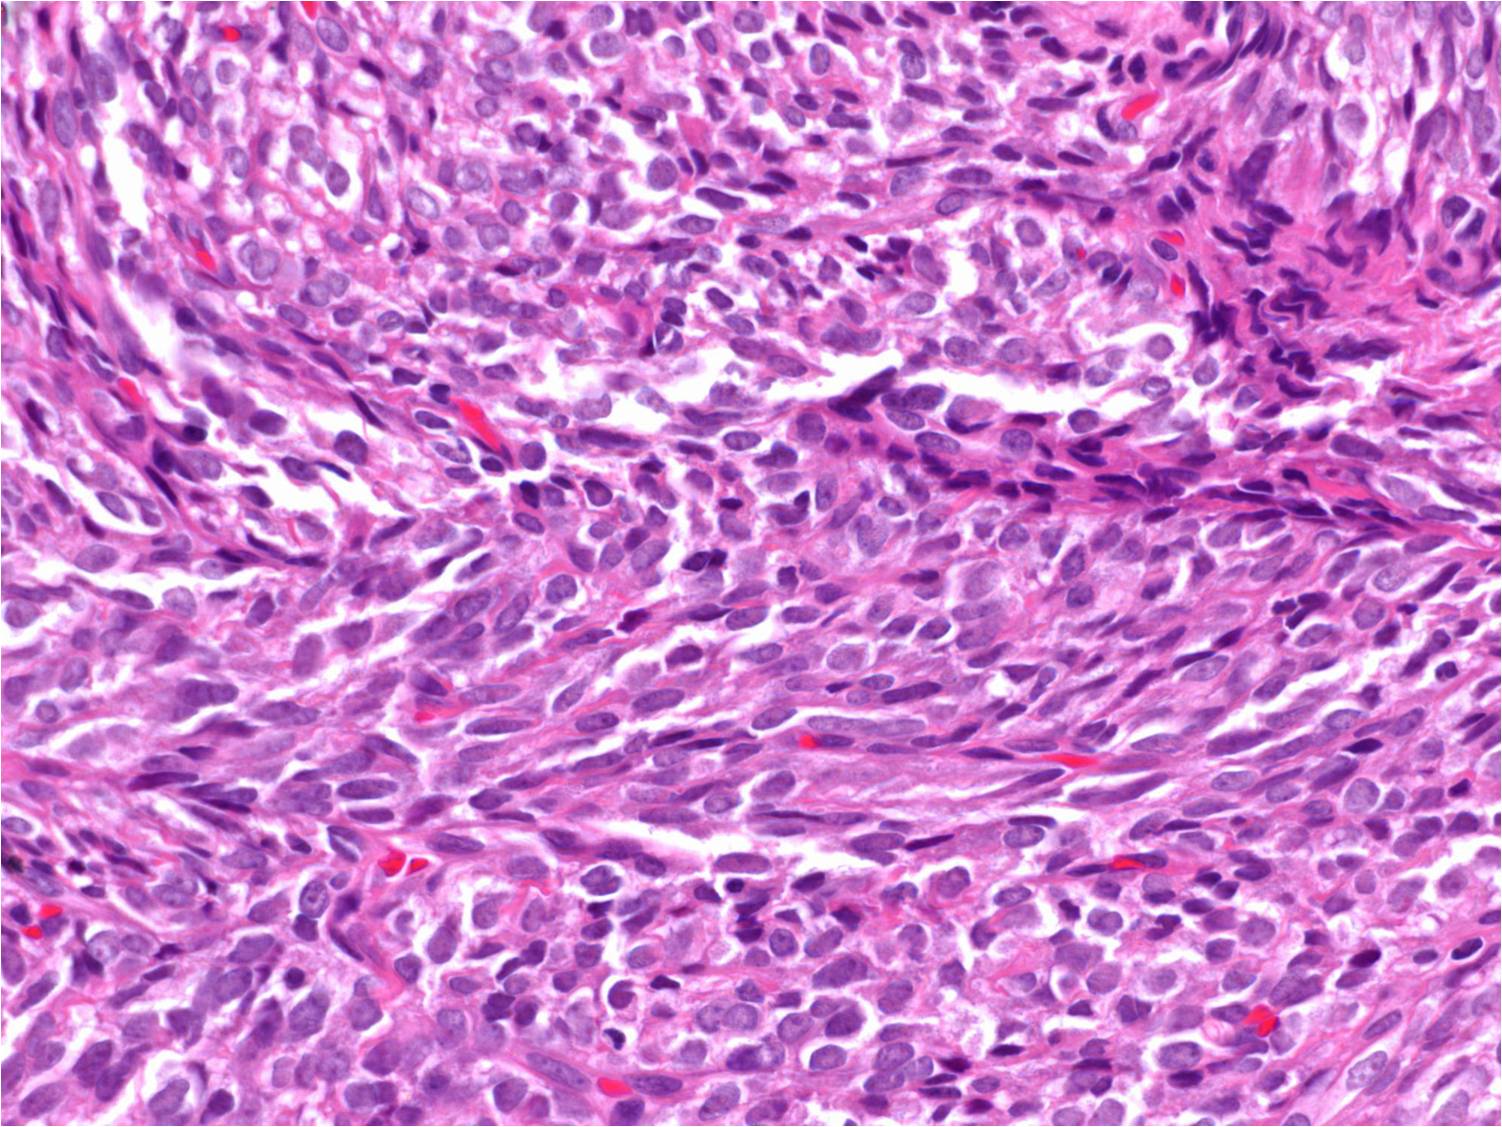

Un estudio liderado por la UCLM y el CSIC identifica dos proteínas clave en el desarrollo de los sarcomas

Los sarcomas son un grupo heterogéneo de tumores poco estudiados y sin terapias dirigidas que actúan específicamente contra el tumor, disminuyendo así la supervivencia de los pacientes y empeorando su calidad de vida, “lo cual es especialmente relevante si consideramos que se trata de un tipo de tumor con una alta prevalencia en la infancia”, destacan los investigadores